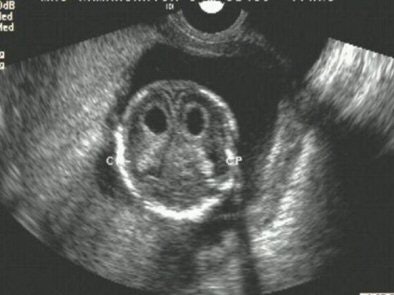

CP cysts over 3 mm in size are taken to be markers. Like other markers, they can also be found in normal fetuses, but are more often found in aneuploid fetuses.

In a series of 27,511 second-trimester scans, Suresh found a 0.7% occurrence of CP cysts. About 65% of them were bilateral, while 35% were unilateral. About 82% were isolated, and 18% were associated with other anomalies.

| Bilateral choroid plexus cysts. All images courtesy of Dr S. Suresh. |

"If the CP cyst is isolated and the patient is otherwise at low risk for fetal aneuploidy, there is no need to offer modified standard obstetric management or offer invasive testing in the antenatal period," Suresh wrote in his paper.